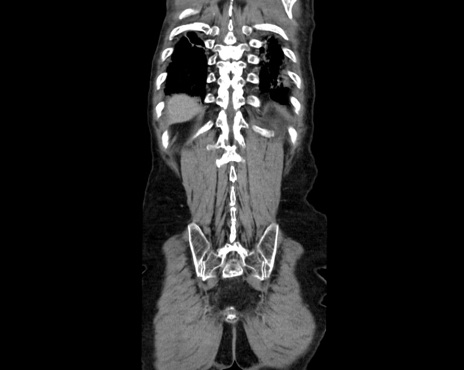

横断像

症例26(冠状断像)

【症例】80歳代男性

【主訴】嘔吐

【現病歴】昨晩2回嘔吐あり、今朝になっても嘔吐あり。来院。

【既往歴】胃潰瘍

【身体所見】意識清明、BT 37.6℃、BP 166/95mmHg、HR 100bpm、SpO2 97%、腹部:平坦・軟、腸蠕動音聴取良好、圧痛なし。

【データ】WBC 21900、CRP 1.4